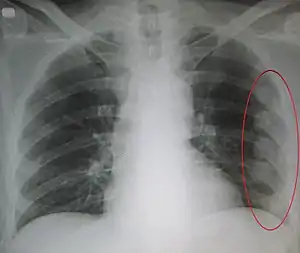

| An X ray showing multiple old fractured ribs of the person's left side as marked by the oval. | |